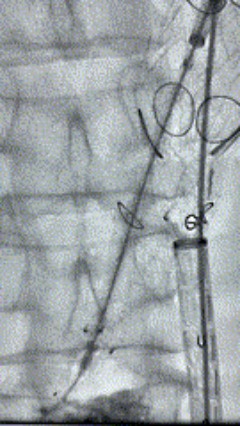

6. 解除束径,打开近端后释放,经肱动脉长鞘超选支架外分支,并进一步超选右侧肾动脉,交换加硬导丝,送入覆膜支架6*50mm和7*60mm各一枚,并予以球囊后扩张,手推造影显影良好。

11.gif    12.gif

7. 经长鞘重新选入左侧外分支,并超选进左肾动脉,沿导丝送入外周血管覆膜支架7*60mm一枚,并予以球囊后扩张,手推造影显影良好。

17.gif